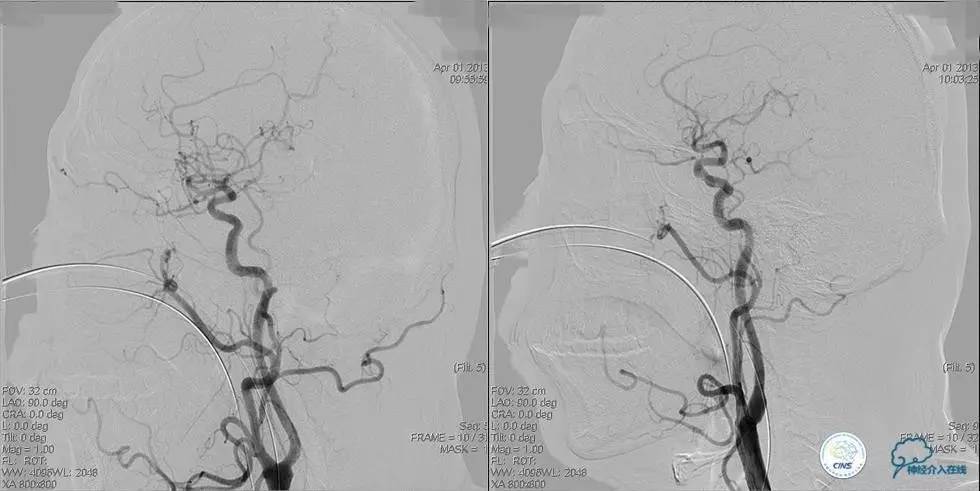

▼入院MR

神经内科保守治疗。

入院第三天,病情转差。

查体:构音障碍加重,右侧肢体肌力下降(近端Ⅱ级,远端0级)。

▼开通

出院情况:头晕症状消失,构音障碍缓解,进食无呛咳,饮水实验(-),右侧肢体远端肌力恢复到Ⅰ级。